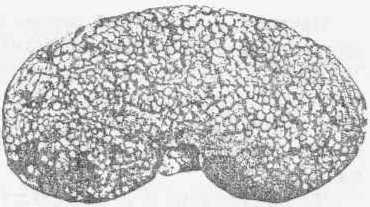

Хронический нефрит у крупного рогатого скота

а — сморщенные дольки

Диффузный хронический интерстициальный нефрит у собаки